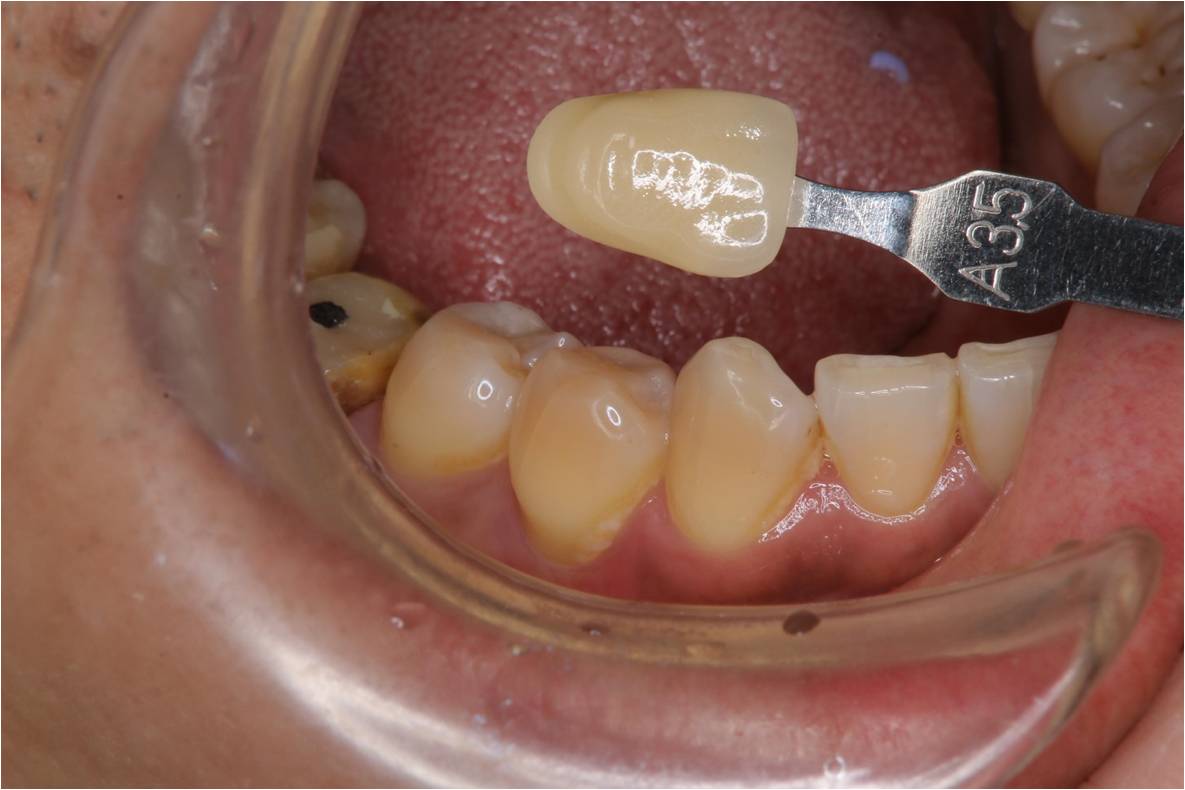

臨床照相比色